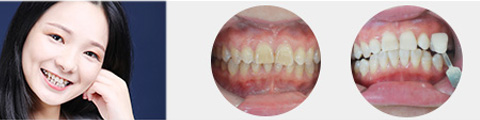

矫正

唯美口腔连锁·汇聚实力专家